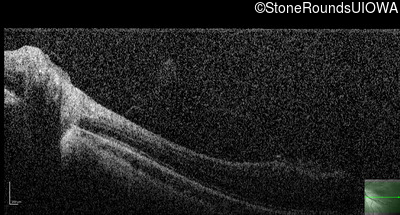

Optical Coherence Tomography - Right - 20/400

Exemplar